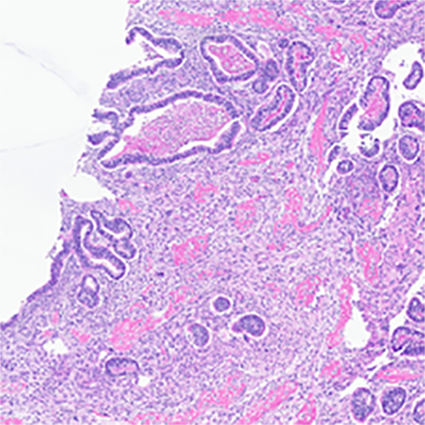

Microscopic examination confirmed carcinosarcoma [figure 3] and revealed heterologous elements, including osteosarcoma and chondrosarcoma [figure 4 and 5]. Metastatic carcinomatous component was identified in the right ovary (1.0 cm) [figure 6], left ovary (0.2 cm), as well as right para-ovarian tissue with tumor cells residing in lymphovascular spaces. The tumor was staged at pathological stage pT3a and a FIGO stage IIIA: local and/or regional spread of the tumor, invading serosa of the corpus uteri and/or adnexa. Finally, the patient was started on adjuvant chemotherapy with carboplatin and paclitaxel.

Figure 4 (left) and figure 5 (right): The sarcomatous component in this case showed heterologous elements in the form of osteosarcoma, large, atypical cells resembling osteoblasts with densely eosinophilic cytoplasm forming osteoid (fig. 3) and chondrosarcoma, atypical, neoplastic chondrocytes, and islands of mature appearing, well differentiated hyaline cartilage (fig. 4 arrow heads)